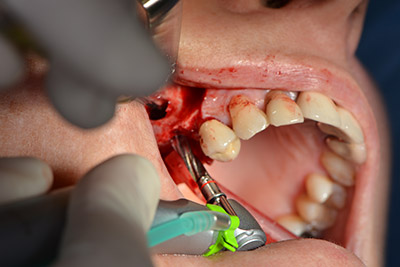

Имплантът е поставен и костта е изградена. В този случай, поради големината на зоната за аугментация, автогенните костни парченца, събрани с костен сондаж след имплантирането в зона 16 и фенестрацията в зона 14, са смесени с костозаместващ материал.

Използвана е абсорбираща мембрана като бариера на букалната страна и покритие на аугментацията. Накрая са поставени устойчиви на слюнка конци (Фиг. 15 до 19).